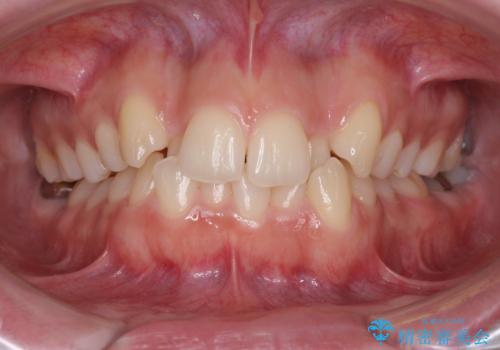

骨格的に左右にずれいている 前歯のデコボコをインビザラインで解消

- 前歯のデコボコと八重歯を気にして来院された患者様です。

叢生の程度は中等度であったため、IPR(歯と歯の間を削る)と歯列の側方拡大をメインに、インビザラインを用いて歯列を改善することとしました。

また、下顎骨の右側変位による右側臼歯の咬合を改善させるよう試みることとしました。